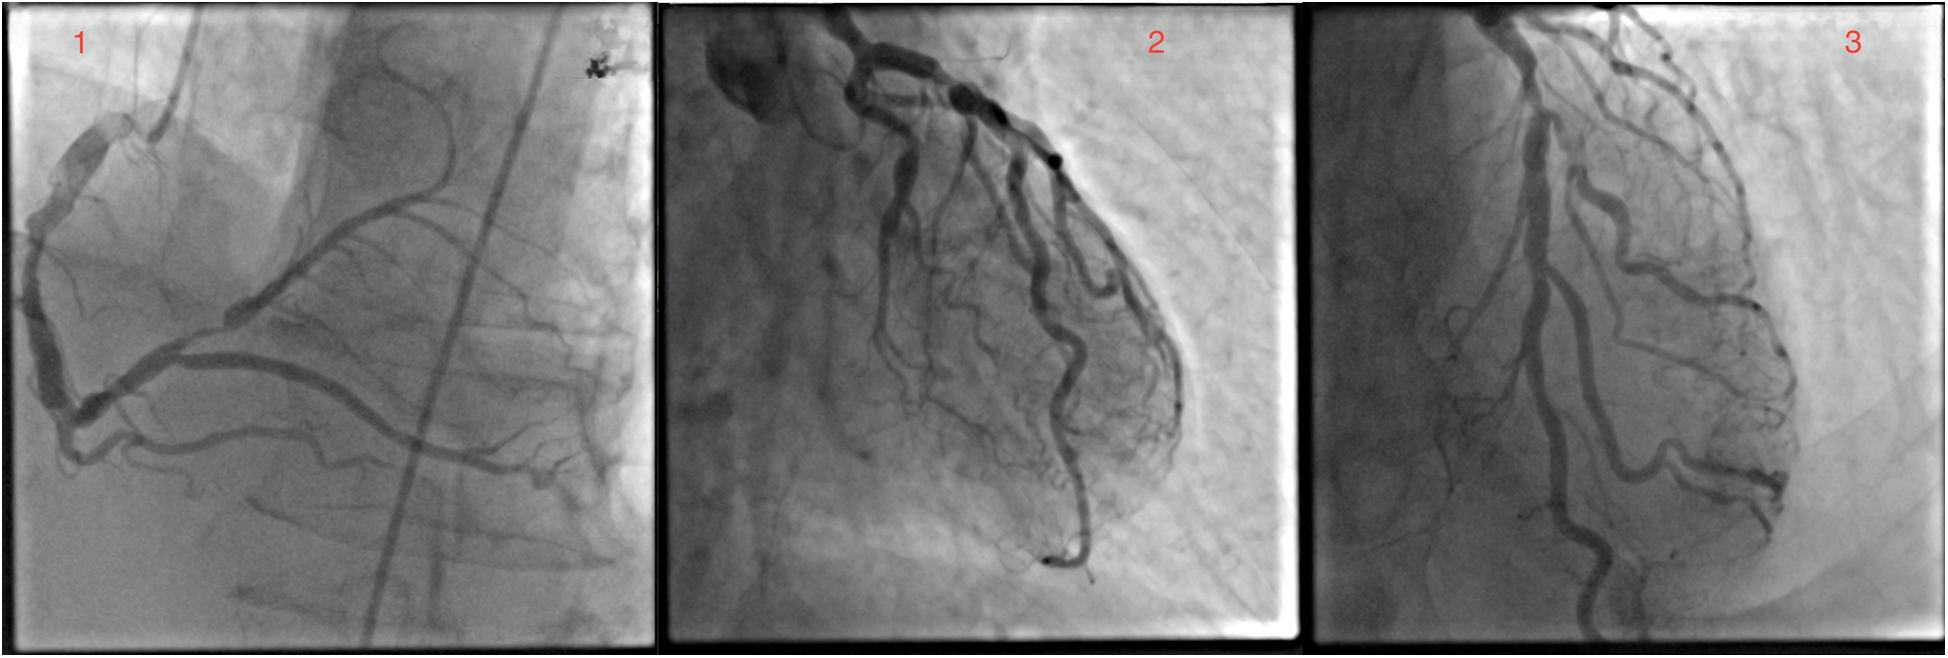

A 73-year-old white male patient had been admitted to the hospital for elective coronary artery bypass grafting. On admission, the patient reported anginous pain at rest without propagation and passes spontaneously, as well as exhaustion from moderate physical effort. In addition, the patient reported losing consciousness on multiple occasions without other neurological signs and symptoms. Risk factors: hypertension, dyslipidemia, former smoker (smoked around 40ty years for 10–20 cigarettes a day), ceased smoking after being hospitalized for MI, and family history of cardiovascular disease, mother and brother dying from myocardial infarction at age 72 and 60 years old, respectively. The patient's everyday medications were: acetylsalicylic acid, clopidogrel, bisoprolol, isosorbide mononitrate, furosemide, KCl, trimetazidine, and rosuvastatin. ECG on admission was: sinus rhythm with 72 bpm, with reduced R wave in inferior leads and negative T wave. The most notable physical manifestation was severely dilated veins in the right arm and a port wine stain on the protrusion of the deltopectoral groove. Further physical examination revealed collapsible veins and pulsing swelling with a trill in the cubital fossa in a projection of the ulnar artery and brachial vein, as well as many pulsating swellings (in the center) on the inner side of the upper arm (Supplementary Video S1). The patient reports having a noticeable vein patern of the right arm from a young age (12 years old) and slowly progressing through life without any physical impairment to quality of life, as such, he never sought any medical help. Four months prior to admission at our Institute, the patient was admitted to cardiology at a local general hospital under suspicion of acute coronary syndrome. At that time, ECG showed sinus rhythm, with inverted T wave in D2, D3, and aVF leads and the highest value of hsTroponin 165 ng/L. In the same hospitalization, coronary angiography and fFR were done and found: ectatic left main with distal stenosis of 60%, ectatic LAD with medial stenosis of 70%, and proximal suboclusion of the diagonal artery, as well as ectatic LCx, with ostial stenosis of 75% and marginal artery with stenosis of 70%; dominant, ectatic and with diffusely atherosclerotic RCA, and PL with proximal stenosis of 90% (Figure 1). Fractional flow reserve (FFR) of LAD was 0.79. The transthoracic echocardiography has shown a normal mitral valve with partially fibrous cusps, normal flow (0.6 m/s), and mitral regurgitation of 1+, a normal tricuspid valve, aortic valve with preserved separation and coaptation with the normal flow (1 m/s), an akinetic basal part of the inferior wall, an akinetic basal part of the posterior wall, and an akinetic base of the ventricular septum, end-diastolic diameter 48 mm, end-systolic diameter 35 mm, and ejection fraction 45%.

Figure 1

Coronary angiography revealed significant left main and three-vessel disease.